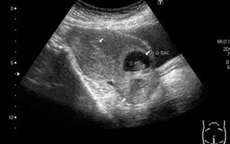

VTV.vn - Sau khi tự đình chỉ thai bằng thuốc tại nhà, cô gái 20 tuổi nhập viện do chửa ngoài tử cung vỡ, chảy máu trong ổ bụng.